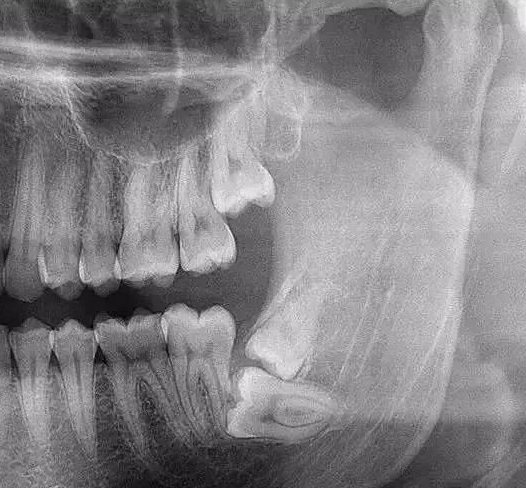

牙齿本身:生长方向,牙根数目,牙根是否弯曲,膨大等。

与重要解剖结构的位置关系:如上颌磨牙与上颌窦的关系;下颌磨牙与下颌神经管的关系;儿童在混合牙列期恒牙与乳牙胚的关系等。可以减少拔牙的风险。预知其他病变:如颌骨内有无埋伏牙,多生牙,囊肿等。